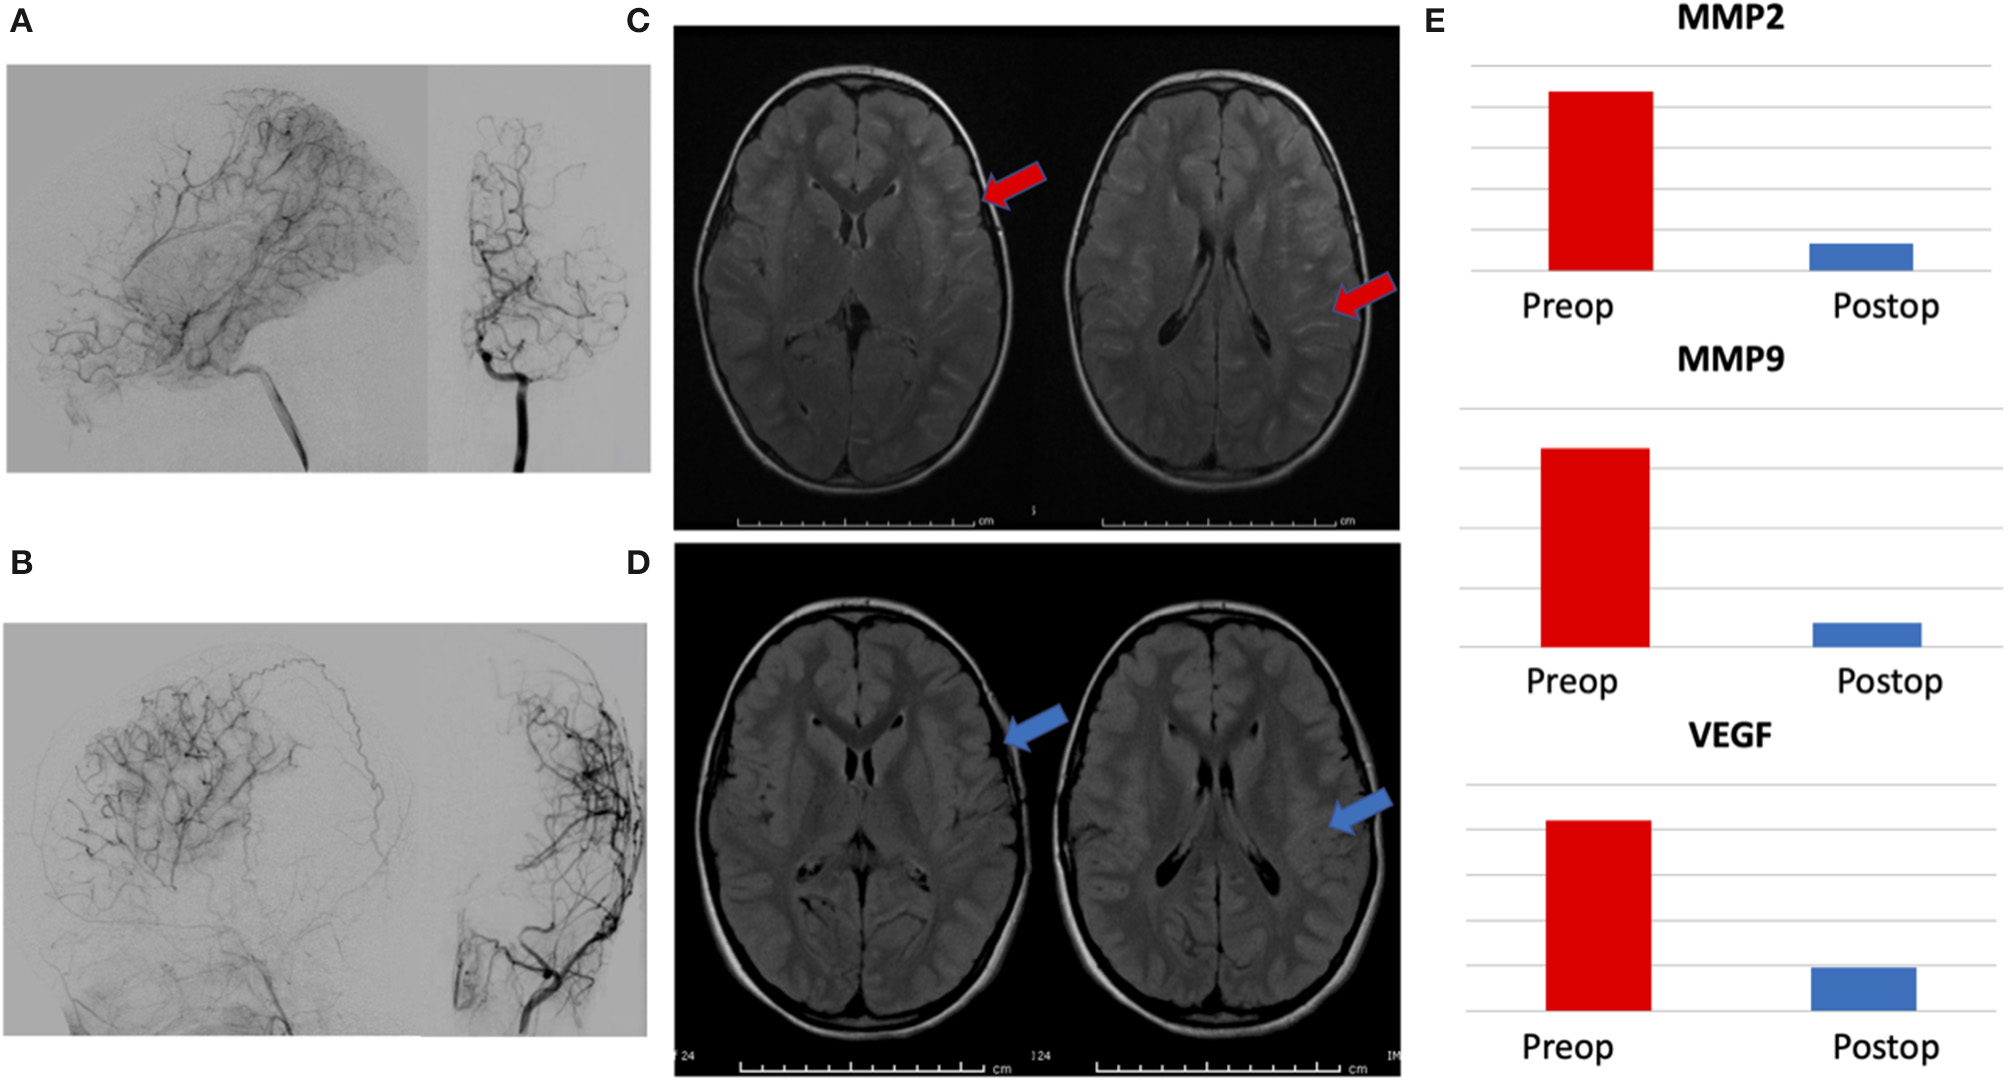

Urinary Biomarkers Change and Correlate With Postoperative Radiographic Response

Urine was collected at 6–12 months postoperatively in patients within this group. A total of 7/32 patients had urine available for analysis. Biomarker levels were compared to preoperative samples (MMP-9/NGAL ELISA kits were no longer unavailable at the time of this delayed analysis, so MMP-2, MMP-9, and VEGF were performed). Pre- and post-operative angiograms were assessed for surgical collaterals (as measured by Matsushima grade) and pre- and post-operative axial FLAIR MRI images were compared for changes in ivy sign (a marker of slow cortical blood flow). All patients had Matsushima A or B collaterals and had reductions in global ivy sign as independently read by neuroradiologists as part of routine clinical care. MMP-2 levels decreased in 6/7 (86%) patients, MMP-9 and VEGF decreased in 5/7 (71%) patients. Representative data from a patient is presented in Figure 3.

Figure 3

Representative patient demonstrating correlation between radiographic changes and biomarker levels. (A) Preoperative angiogram with lateral and AP views of internal carotid artery injection showing Suzuki II-III moyamoya, (B) 1 year postoperative angiogram with lateral and AP views of external carotid injection showing Matsushima A surgical collaterals, (C) preoperative axial FLAIR MRI images demonstrating hyperintense sulcal signal—ivy sign, (red arrows) and (D) postoperative images showing marked resolution of ivy sign (blue arrows). (E) Reduction in postoperative levels of urinary biomarkers MMP-2, MMP-9, and VEGF, correlating with radiographic evidence of successful revascularization.

There is precedent to use biomarkers as tools to monitor response to therapy. Specifically, in moyamoya disease and other vascular diseases, evidence exists that levels of MMPs and VEGF are elevated in the setting of chronic ischemia and—once successful revascularization occurs and the ischemia is reduced—the ischemic stimulus driving the upregulation of MMP and VEGF is decreased, with a concomitant reduction in the levels of these markers (27, 30, 49, 53–55). As documented in previous work from our lab and others, the CNS levels of these molecules are directly related to urinary levels, with previous reports linking source tissue, CSF, serum and urine (3–6, 21, 37, 56). The working model is that the end-organ (brain) experiences chronic ischemia from the moyamoya arteriopathy and is elaborating these angiogenic factors at baseline in order to develop compensatory collateral development. Once surgical revascularization occurs, transient elevations in these factors enhance surgical collateral growth until the ischemia is corrected (a process well-documented by postoperative imaging studies, showing improved perfusion and surgical collaterals on angiogram), at which point the ischemic stimulus no longer exists, and the production of pro-angiogenic molecules decreases. While we do not have sampling from the immediate postoperative period (days to weeks), we would hypothesize that we would see marked elevations in pro-angiogenic biomarkers (such as VEGF and MMPs) within this window until enough revascularization occurred to normalize perfusion (usually several weeks to months after indirect revascularization). In support of this hypothesis, our data shows that these biomarkers are elevated pre-surgery and decrease post-operatively in concordance with radiographic evidence of effective surgical revascularization on angiogram and improved hemodynamic perfusion on MRI with reduced ivy sign (Figure 3).